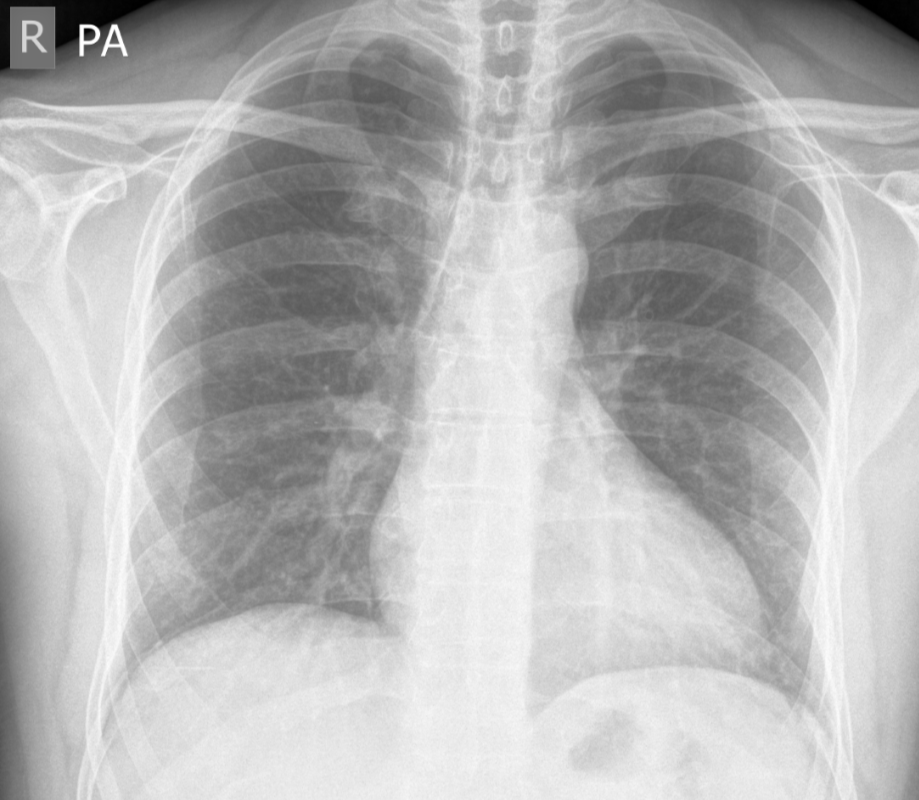

Left apical pneumothorax